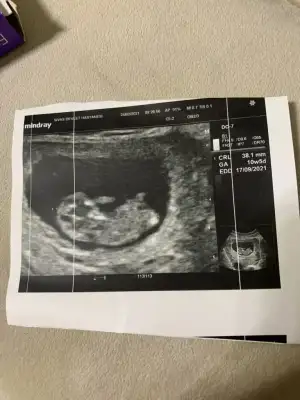

Kızlar yüklemeyi başarabildiysem bana da cinsiyet yorumu yapabilir misiniz :) ilk bebeğimiz 8+6 idi 9+1 gözüktü ultrasonda :)

• IMG-20210223-WA0008.webp

IMG-20210223-WA0008.webp

28 KB · Görüntüleme: 81

Canım nub pek belli olmuyor gördüğüm o ise kız gibi 30 derece altında :)) yaa inşallah 12.hafta bende böyle bir şey görürüm bin kere maşallah canım. 💙